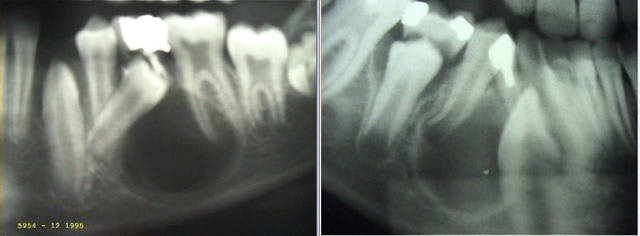

Mais puisqu’il faut que je vous aide… voici deux autres cas que j’ai traité en son temps de la même façon. Sur le second cliché, la 43 est carrément déplacée en mésial. En observant bien, vous devriez trouver comment j'ai procédé !

L'image n'avait pas suivi...